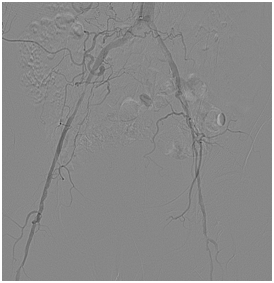

颈动脉内膜剥脱术